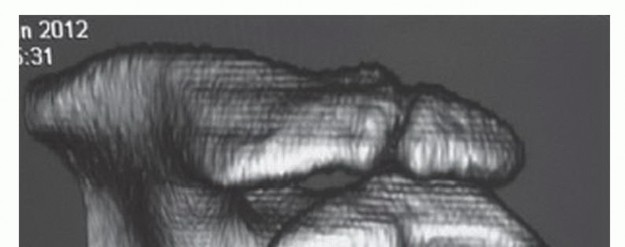

Imaging studies are reviewed to ensure the preoperative diagnosis is correct. Particular attention should be paid to acromial morphology, the status of the AC joint, and evidence of rotator cuff pathology, as these disease processes often coexist. The preoperative supraspinatus or acromial outlet view gives the surgeon an accurate measurement of the amount of bone that must be resected from the anterior acromion to convert the acromial morphology to type I. 16 If the AC joint has developed osteoarthritic changes, the presence of an inferior AC joint osteophyte may contribute to subacromial impingement. The presence of AC arthritis may not be clinically symptomatic; thus, coplaning of the inferior AC joint should be performed with the subacromial decompression. If the AC arthritis is symptomatic, distal clavicle resection should be performed in conjunction with subacromial decompression. Preoperative knowledge of a rotator cuff tear is important for surgical planning of equipment, resources, and operative time as well as patient informed consent, recovery time, and time lost from work. Os acromiale may be visualized on outlet and axillary lateral radiographs, MRI, or CT(FIG 2). Both fixation of an os 29,30 or arthroscopic excision23 can lead to improved clinical outcomes, depending on the location of the unstable fragment. Acromioplasty or arthroscopic resection may be performed for a symptomatic os at the mesoacromiale level. 31 Failure to recognize associated pathology is a common source of surgical failure. Examination under anesthesia of the affected shoulder is done before positioning. Passive range of motion is documented. The patient should be evaluated for a posterior capsule contracture, which can exacerbate impingement symptoms. Release of the posterior capsule with manipulation or arthroscopic release can improve a significant posterior capsule contracture.

FIG 2 • Three-dimensional CT image demonstrating an unstable mesoacromiale.